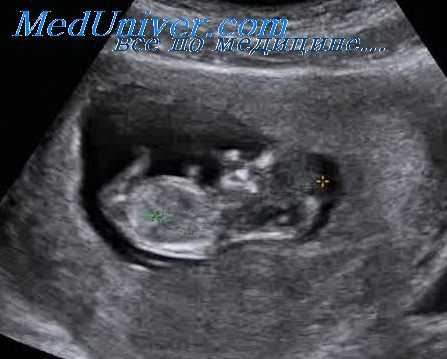

Эхография позволяет определить зиготность и число хориальных и амниотических оболочек, а также описать расположение плаценты, предлежание плодов и диагностировать такие осложнения в течении беременности, как диссоциация развития плодов, наличие патологических сосудистых анастомозов, дисбаланс объема околоплодных вод в разных плодовместилищах и формирование коллизии (спутывания) пуповин.